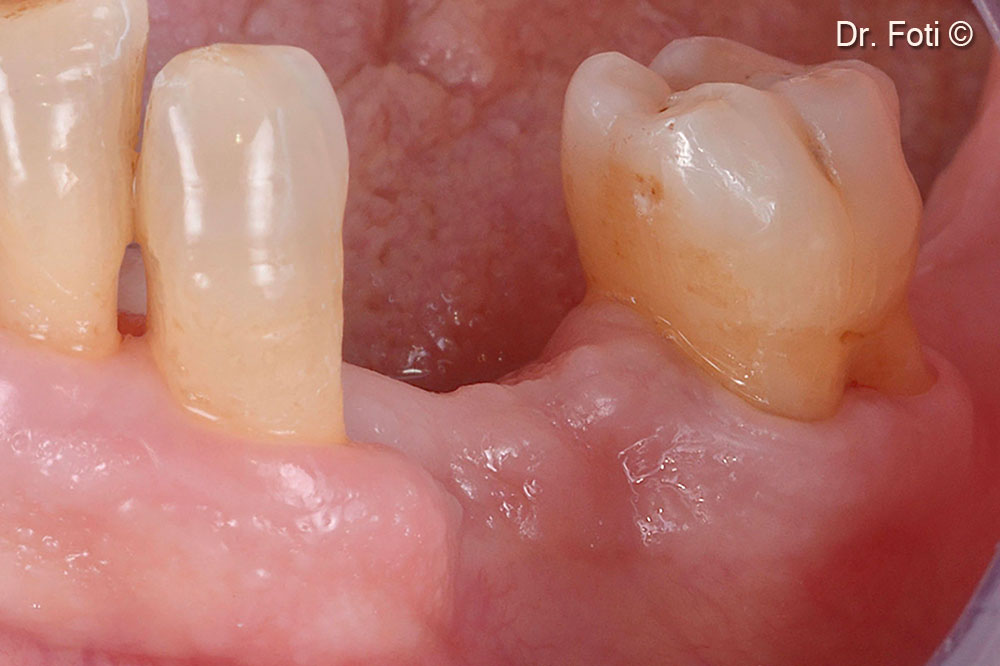

New anatomy and volume of the site after six months.